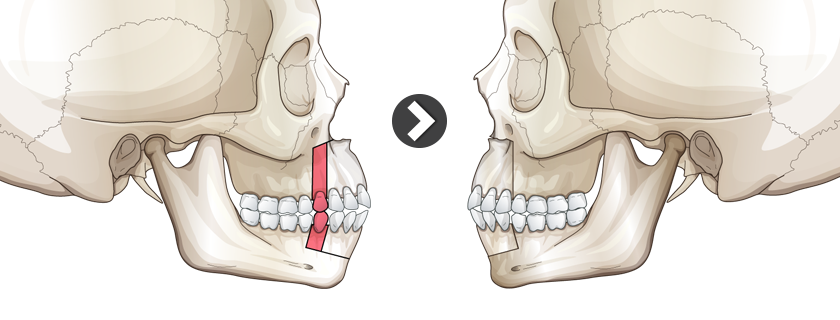

that would work but would probably recess the fuck out of me but it is always an optionView attachment 4175991

found this, no fucking clue what it is but looks like it does the job and recesses your maxilla pretty sure

I have no fucking clue i just found it on googlethat would work but would probably recess the fuck out of me but it is always an option

yeah I found it aswell, I've never seen anything like it beforeI have no fucking clue i just found it on google